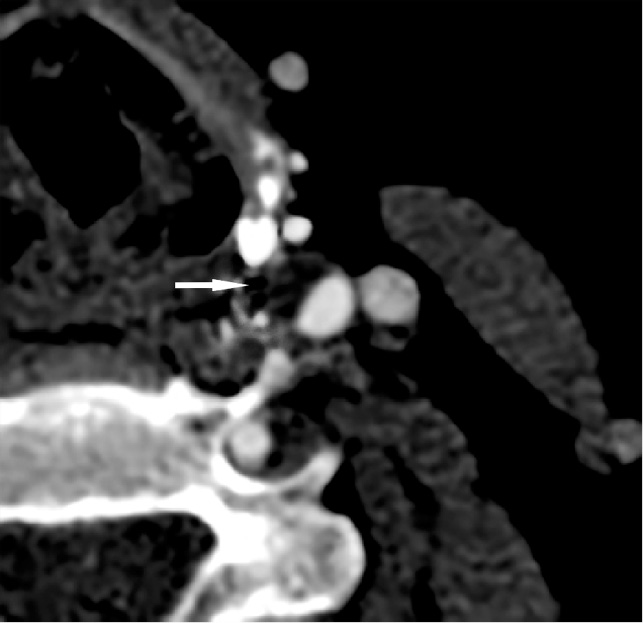

Представление о степени стеноза ВСА и стабильности атеросклеротической бляшки, ее устойчивости к воздействию избыточного давления были получены на основании данных КТ АГ (рис. 6, 7).

Рис. 6. Компьютерная томограмма пациента с нестабильной атеросклеротической бляшкой. Определяется многокамерная полость внутри атеросклеротической бляшки с жидкостным компонентом (белая стрелка)

Fig. 6. Сomputed thomography scan of a patient with unstable atherosclerotic plaque. A multi-chambered cavity inside an atherosclerotic plaque with a fluid component is determined (white arrow)